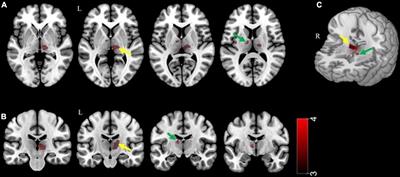

Original Research

Published on 15 Mar 2023

in Brain Imaging Methods